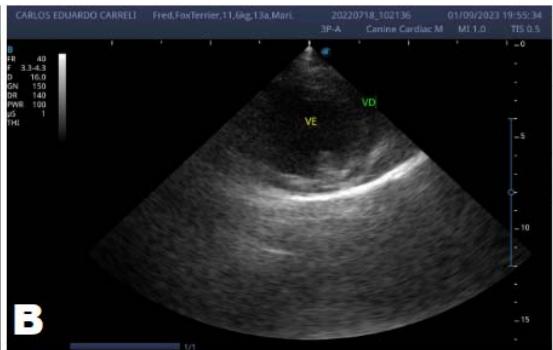

One year later, the animal returned for a new evaluation, repeating the ECHO (Figure 2), which showed the progression of the increase in the left atrium. The electrocardiogram (ECG) (Figure 3) shows baseline sinus arrhythmia with the presence of a premature ventricular complex (Figure 4). Owners report drowsiness, hyporexia, and syncope. However, they did not present tiredness or cough. Blood pressure was 80 mmHg.

Figure 2: Echocardiogram (2022): observed increase in the left atrium and ventricle; thickened/degenerated mitral valve (A); observed in a Doppler study, turbulent systolic flow within the left atrium, characterizing significant mitral valve insufficiency (B); systolic turbulent flow within the right atrium, representing mild tricuspid valve insufficiency (C); hemodynamic assessment - maximum velocity gradient mitral regurgitation: $3.51\mathrm{m / s} / 49.22\mathrm{mmHg}$; observed left ventricular diastolic dimension above normal limits with normal systolic function parameters, characterizing systolic dysfunction; preserved diastolic function

In 2022, the animal returned for annual exams one year after the diagnosis. The ECHO showed an increase in the left atrium and ventricle, thickened/degenerated mitral valve (Figure 2), preserved diastolic function, and low probability of pulmonary hypertension; the ECG detected an increase in the duration of the P wave and the QRS complex (Figure 3), suggestive of atrial and left ventricular overload, baseline sinus arrhythmia with the presence of a premature ventricular complex.